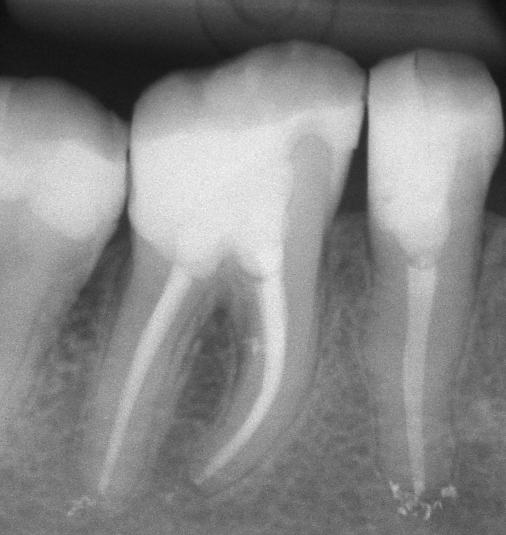

Apertura della corona fino ad arrivare alla camera pulpare (tale trattamento viene eseguito tramite anestesia locale). Si rimuove la polpa e si cercano i canali radicolari del dente, una volta trovati si estirpano i nervi. Si allargano e si puliscono i canali del dente, (tramite strumenti al Nichel titanio o strumenti manuali) prendendo anticipatamente le misure dei canali (per non uscire oltre apice). Si disinfettano i canali e si eseguono vari lavaggi tra un passaggio e un altro per elimininare il fango dentinale. Il medico a questo punto verifica la possibilità di chiudere definivamente i canali o lasciare il dente in prova, inserirendo nei canali un disinfettante e eseguendo una chiusura provvisoria. Al momento di chiudere il dente definivamente, questo viene preparato rieseguendo le misure dei canali da chiudere ed usando per la stessa lunghezza del canale, un cono di guttaperga del diametro necessario. Si scalda il cono in guttaperga e si inserisce nel canale. Durante il trattamento endodondico vengono effettuati una serie di esami radiografici per verificare i risultati, le lunghezze, la forma dei canali.

L'esame radiografico, fondamentale per porre diagnosi in odontoiatria, in endodonzia è irrinunciabile perché è l'unico strumento che ci permette di "vedere" all'interno della radice del dente, è quindi molto importante la possibilità di effettuare lastre con apparecchiature digitali che emettono un quarto della dose di raggi emessa da un radiografico tradizionale e che permettono di conservare la radiografia endorale in una cartella informatica del paziente senza possibili alterazioni nel tempo.